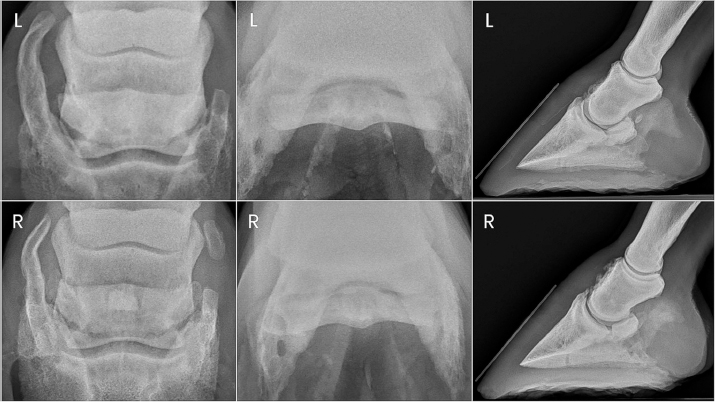

Horse 2 remained comfortable postoperatively with no appreciable lameness until approximately day 129, at which time a mild and inconsistent grade 4/5 RF lameness was noted. On day 136 post-PDN, the gelding was presented for student teaching of radiographic techniques. Radiographs were taken of both front digits, which revealed a parasagittal fracture of the right forelimb navicular bone and mild hyperextension of the right DIPJ (Fig. 4). Ultrasound revealed severe fiber pattern disruption of the DDF tendon suggestive of severe tendinopathy or rupture in the distal pastern region of both the right and left forelimbs. Humane euthanasia was elected due to the severity of the pathology and poor prognosis. Postmortem MRI was performed on both forelimbs revealing marked bilateral navicular bone degeneration with an obliquely oriented complete fracture of the lateral quarter of the navicular bone on the right forelimb, and bilateral severe DDF tendinopathy with almost complete rupture of the DDF tendon at the level of the navicular bone (Fig. 4). Additional findings of note in both forelimbs were significant navicular bursitis with probable bursal adhesions, enthesopathy of the flexor surface of the third phalanx at the DDF tendon insertion site, and impar, collateral sesamoidean ligament, and distal digital annular ligament desmopathy.

Fig. 4. Ante-mortem radiographs and postmortem MRI images of horse two showing the right forelimb navicular bone fracture and bilateral DDF tendon compromise.